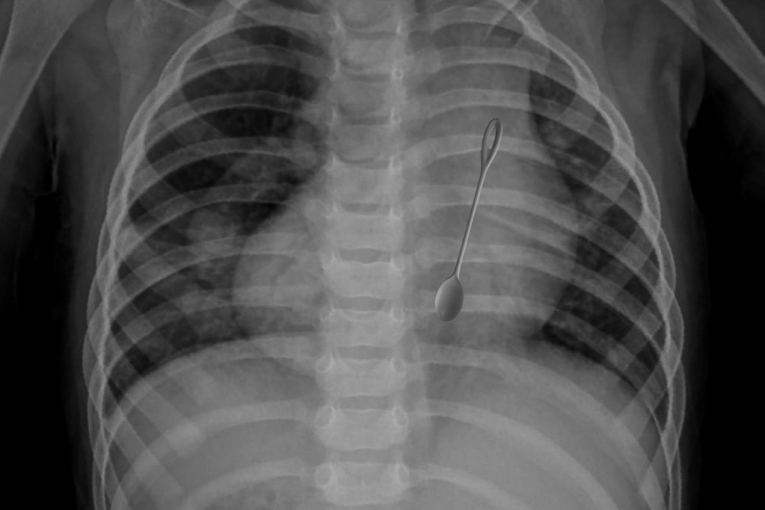

Pacijent je hitno hospitalizovan. Rendgenski snimak abdomena pokazao je da se strano telo zaglavilo u želucu.

Rendgenski snimak koje je objavilo ministarstvo prikazuju dečju kašiku s figuricom novogodišnje jelke na kraju drške.

- Izvršeno je hitno endoskopsko uklanjanje stranog predmeta - metalne kašike dužine 14 centimetara. Postoperativni period je protekao bez ikakvih komplikacija - saopšteno je.